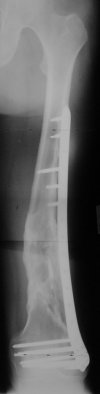

I presented a series of ~25 such cases at EuroTrauma'2004. Many cases were discussed here. I attach am example. Look also recent cases at http://www.hwbf.org/hwb/conf/alex58/scfx.htm,

http://www.hwbf.org/hwb/conf/alex63/alex63.htm

At that moment we had in stock only the 10 mm solid nails so of course there was no idea about early weight bearing. But it was quite enough for early knee ROM excersises (see attached). Two locking screws through the distal block provided that.